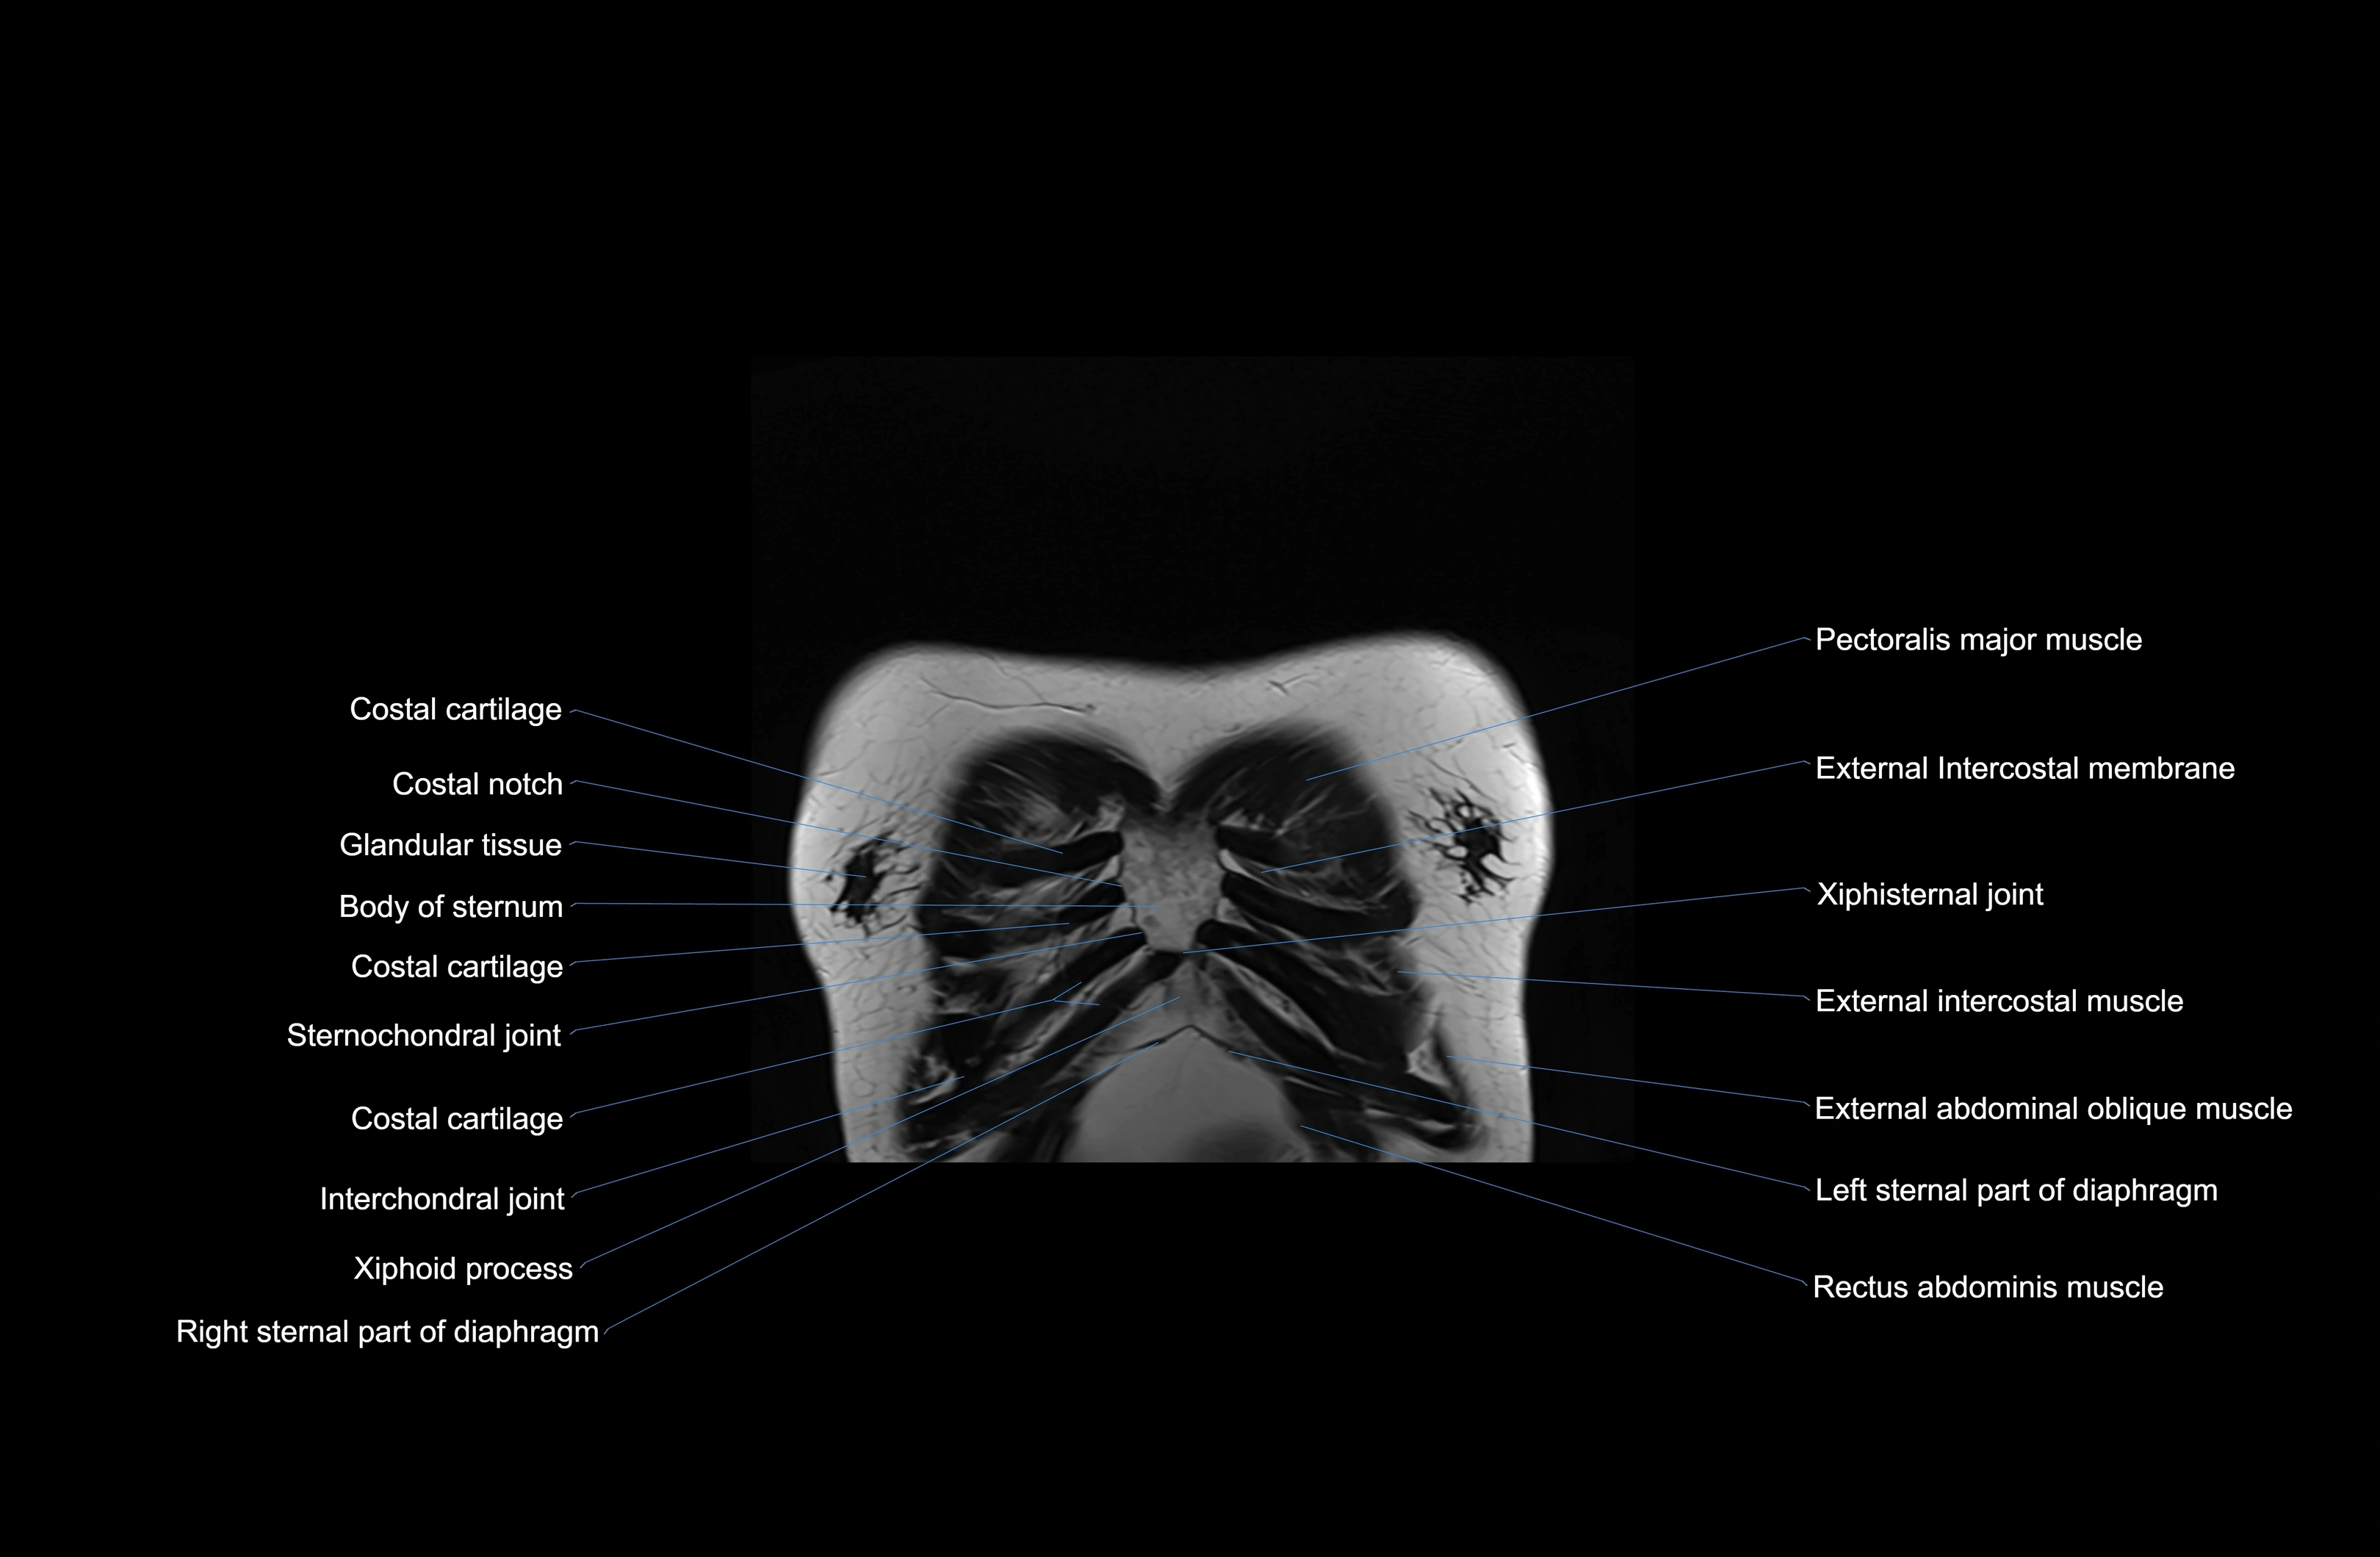

MRI images